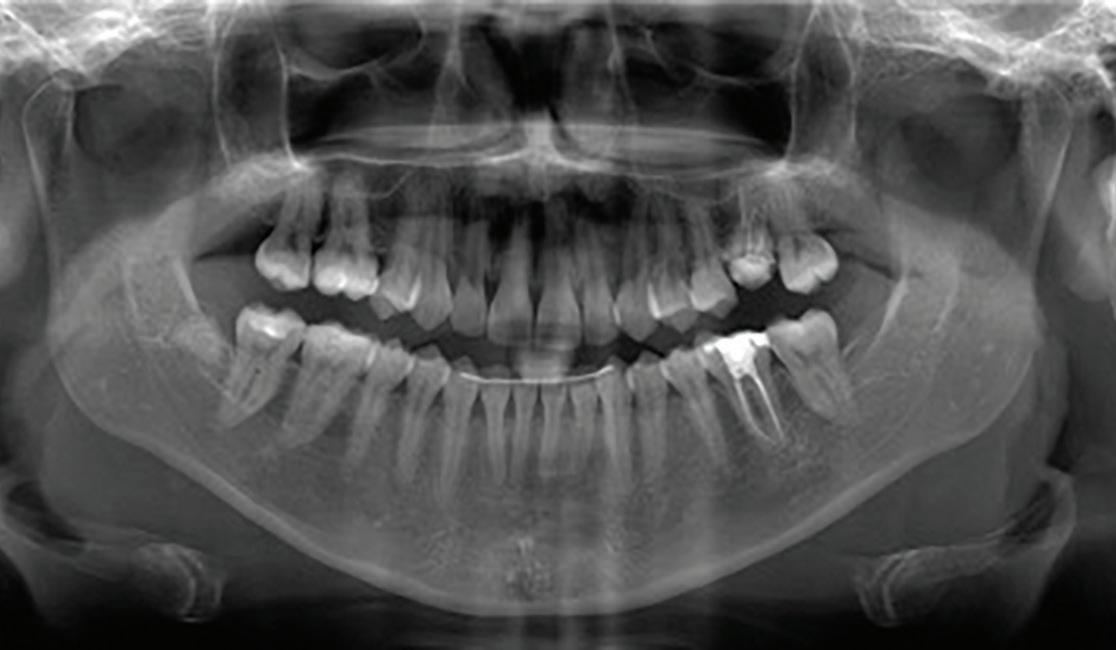

Root migration after coronectomy of impacted mandibular third molars: case reports

Gustavo Henrique de Souza Silva Enzo Balestrero

Jéssica Lemos Gulinelli

Pâmela Leticia dos Santos